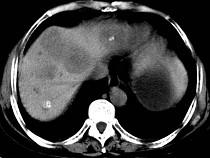

问题 女,55岁,腹胀,肛门闭气,消瘦乏力,肝区疼痛,CT检查如图,最可能的诊断为 ( )

选项 A.多发性肝脓肿 B.肝癌肝内转移 C.肝淋巴管瘤 D.肝脏囊腺瘤 E.结肠癌肝转移

答案 E